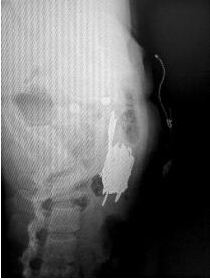

曲颖的x光片显示,她的体内有一捆剪刀。

5月13日上午,42岁的曲颖(化名)躺在省直中医院普外科的病床上。11日晚上,其因腹痛被路人发现后拨打120,送往医院救治。X光片显示,其中下腹部横亘着一捆剪刀,曲颖称自己为了躲避被抓,便吞下了这些剪刀,大概有10把。

当天晚上,省直中医院急诊科对曲颖进行了抢救,随后送往普外科住院治疗,从X光片可见一捆剪刀横亘在其中下腹部,剪刀长近12厘米。医生诊断腹部肠管少量积气,未见明显液气平面和肠管扩张。曲颖身无分文,普外科医生为她进行输液治疗。